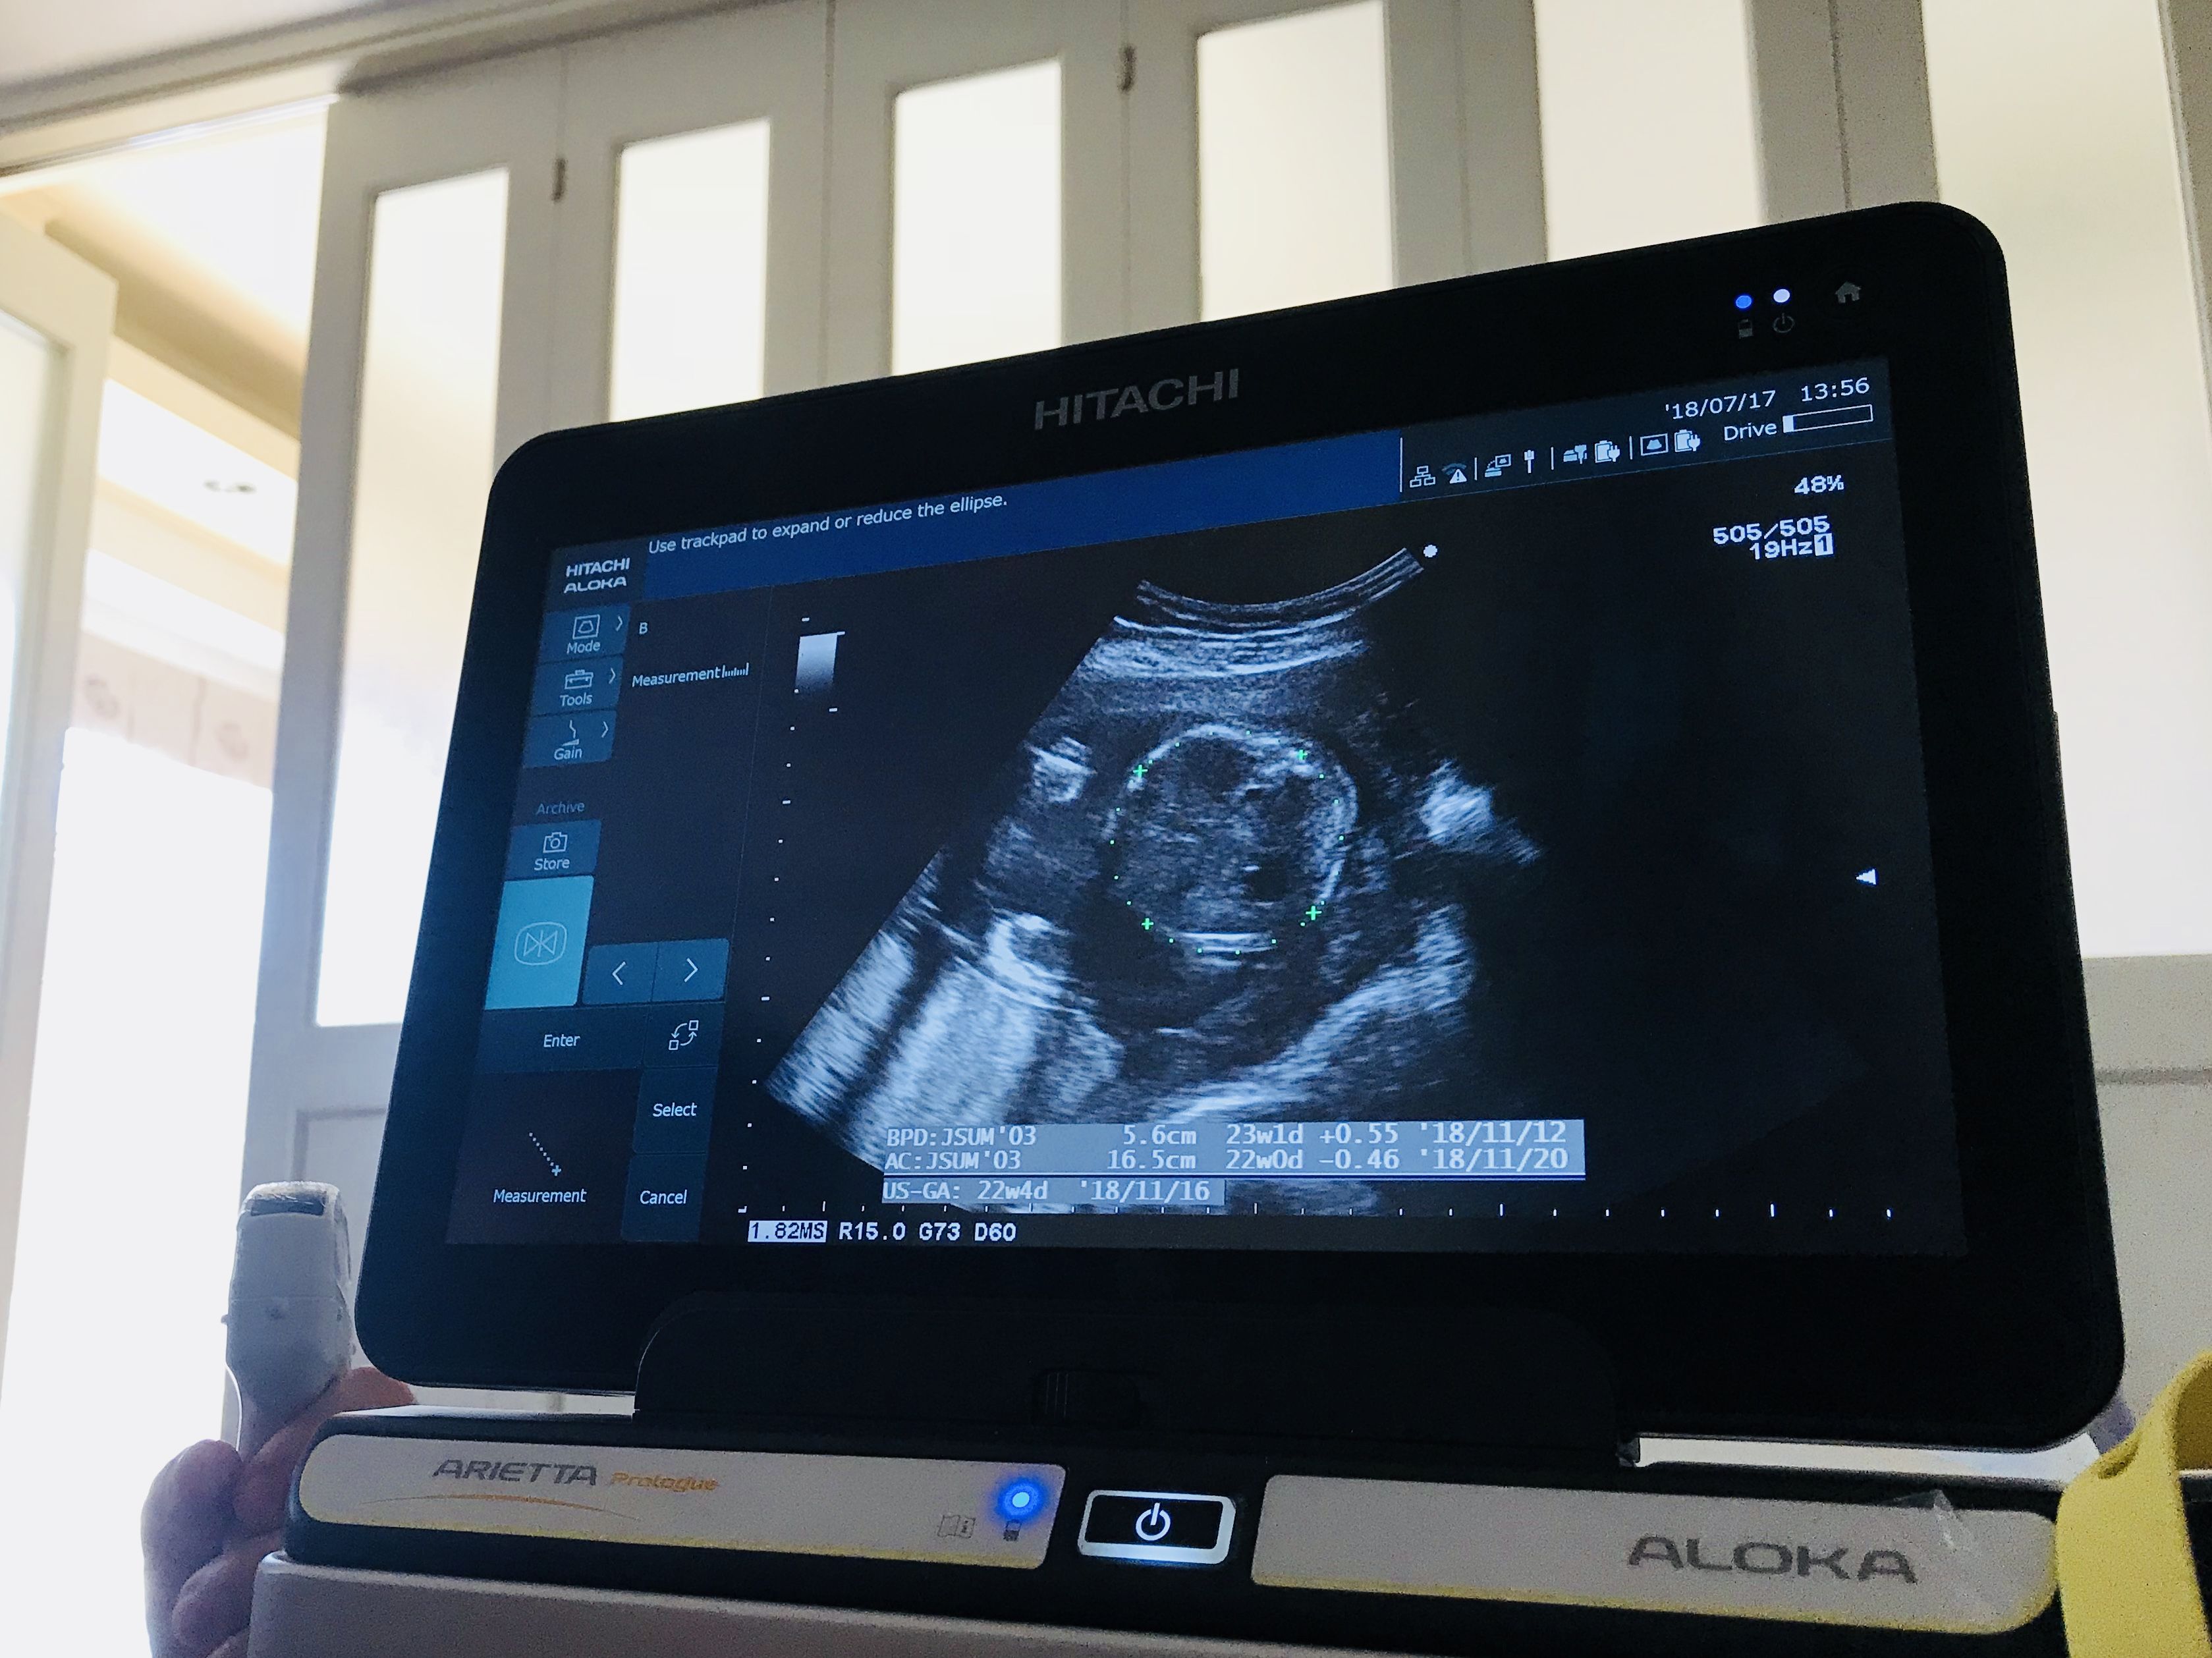

そんな不安を抱えつつ、この間検診に行って超音波エコーを見てもらったら、「赤ちゃんの推定体重は498gでしょう」って言われました。

【豆知識】赤ちゃんの推定体重ってどうやってわかるの?

ちなみにみなさん、赤ちゃんの推定体重ってどうやって算出してるかご存知ですか??

私は今まで知らなかったんですけど、この間の検診の時に超音波エコーを見ながら先生が

「赤ちゃんの頭の大きさとかお腹周り、太ももの長さを測って、それを複雑な式に当てはめるんですよ〜」

って教えてくれました。

へ〜〜〜!先生が複雑な式って言うんだから、相当複雑な式なんだろうな。気になったので、その複雑な式とやらをググってみました!そしたら、

赤ちゃんの体重、頭の大きさ、お腹周り、太ももの長さを、それぞれ、推定体重(EFW)、児頭大黄径(BPD)、腹囲(AC)、大腿骨長(FL)って呼ぶらしいんですけど、↓のような式になるそうです。

EFW(g)=1.07×BPD3+0.30×AC2×FL